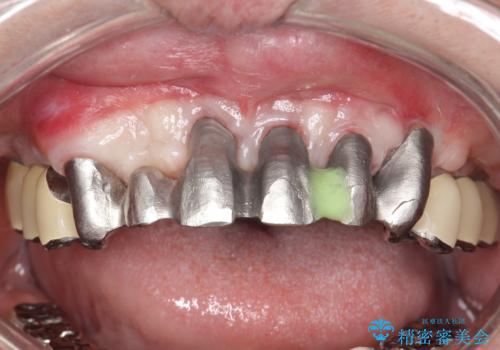

歯周病におかされた前歯の再建治療

かぶせ物の種類:PFM full bake